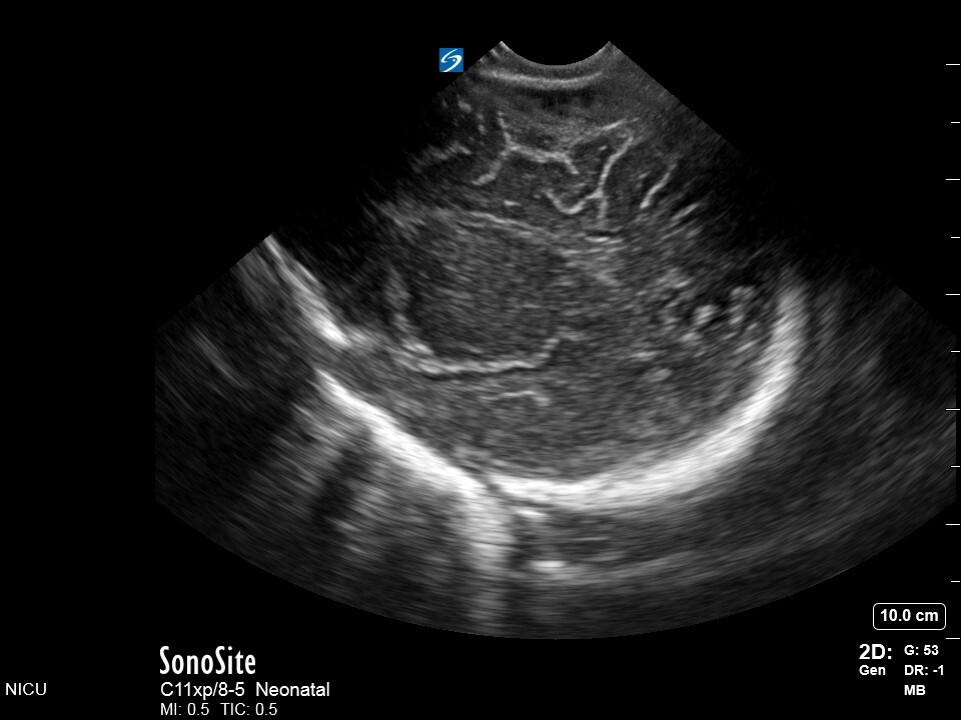

Neonatology S3 1 Image